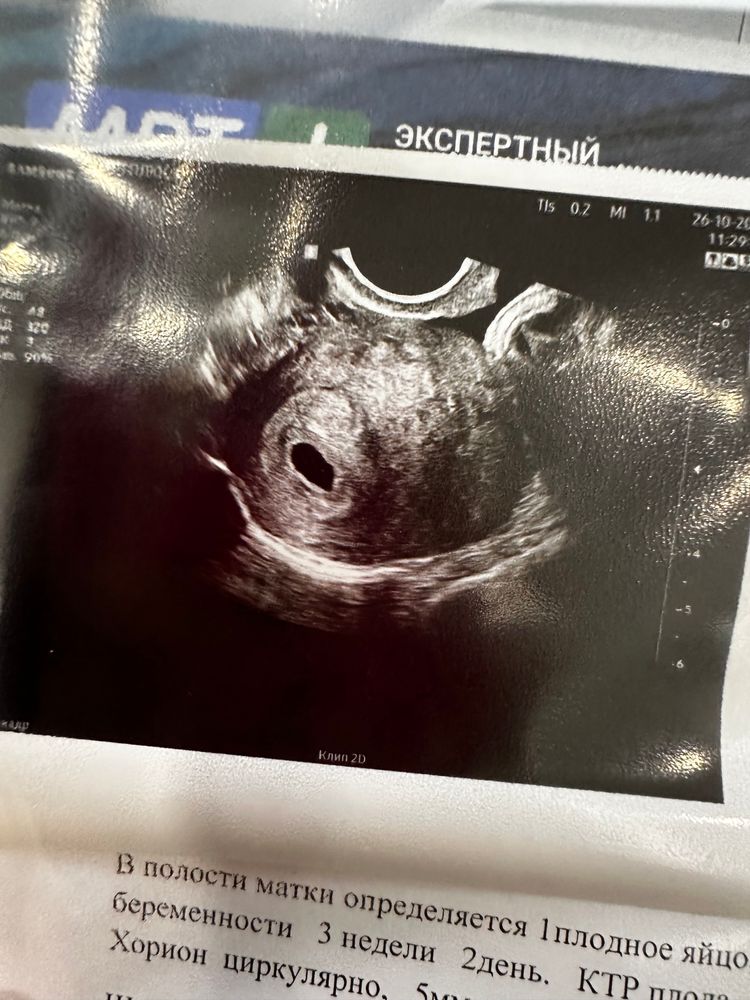

devochka_sem , сделала узи , сказали прийти через 10-14 дней 😄 Изображение